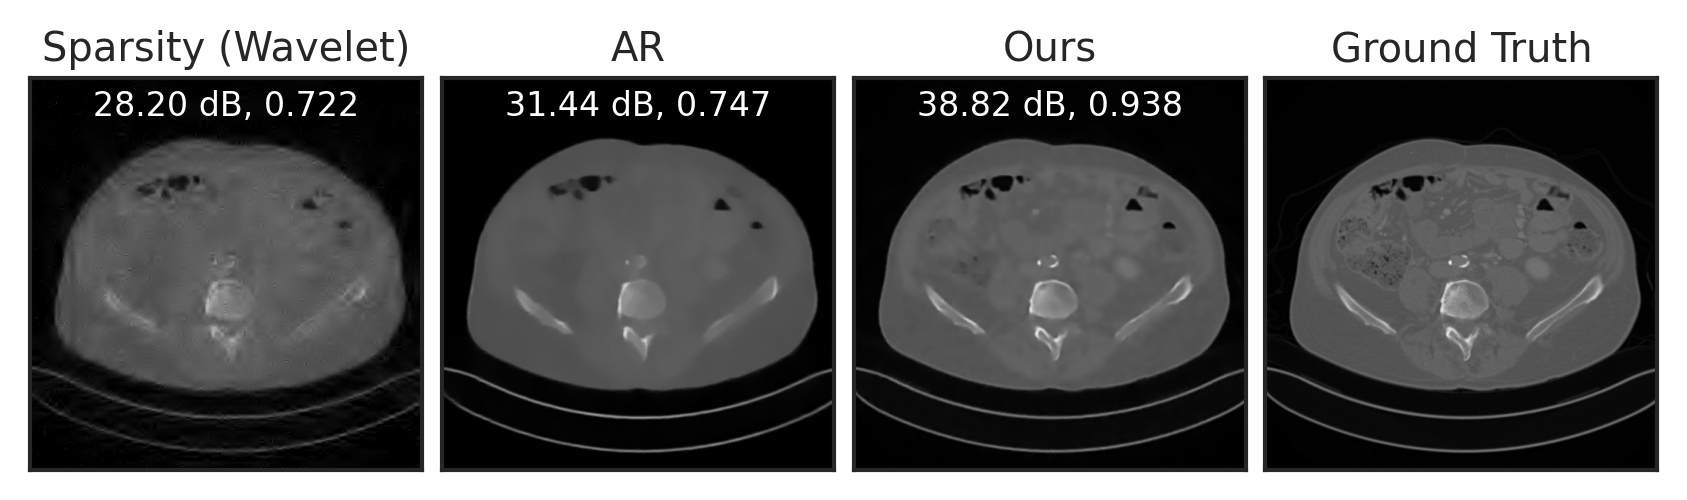

Sparse View Tomographic Reconstruction

Compressed Sensing

Deblurring